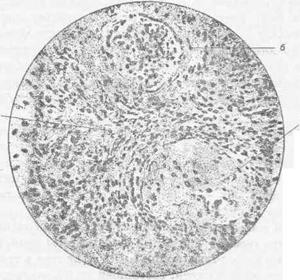

Гломерулонефрит (Glomerulonephritis) — воспалительный процесс почек инфекционно-аллергической этиологии с преимущественным поражением клубочкового аппарата нефрона (рис. 119).

Рис. Гломерулонефрит у свиньи